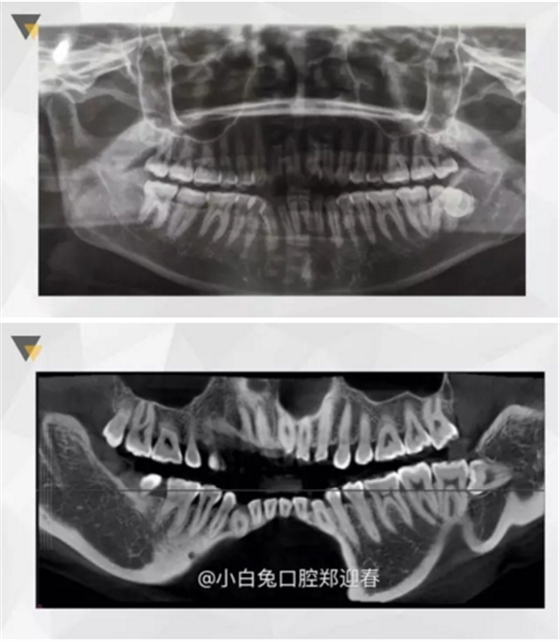

再看看逆襲的尖牙阻生。。。

小泥鰍

橫位

錯(cuò)位

大尺度異位